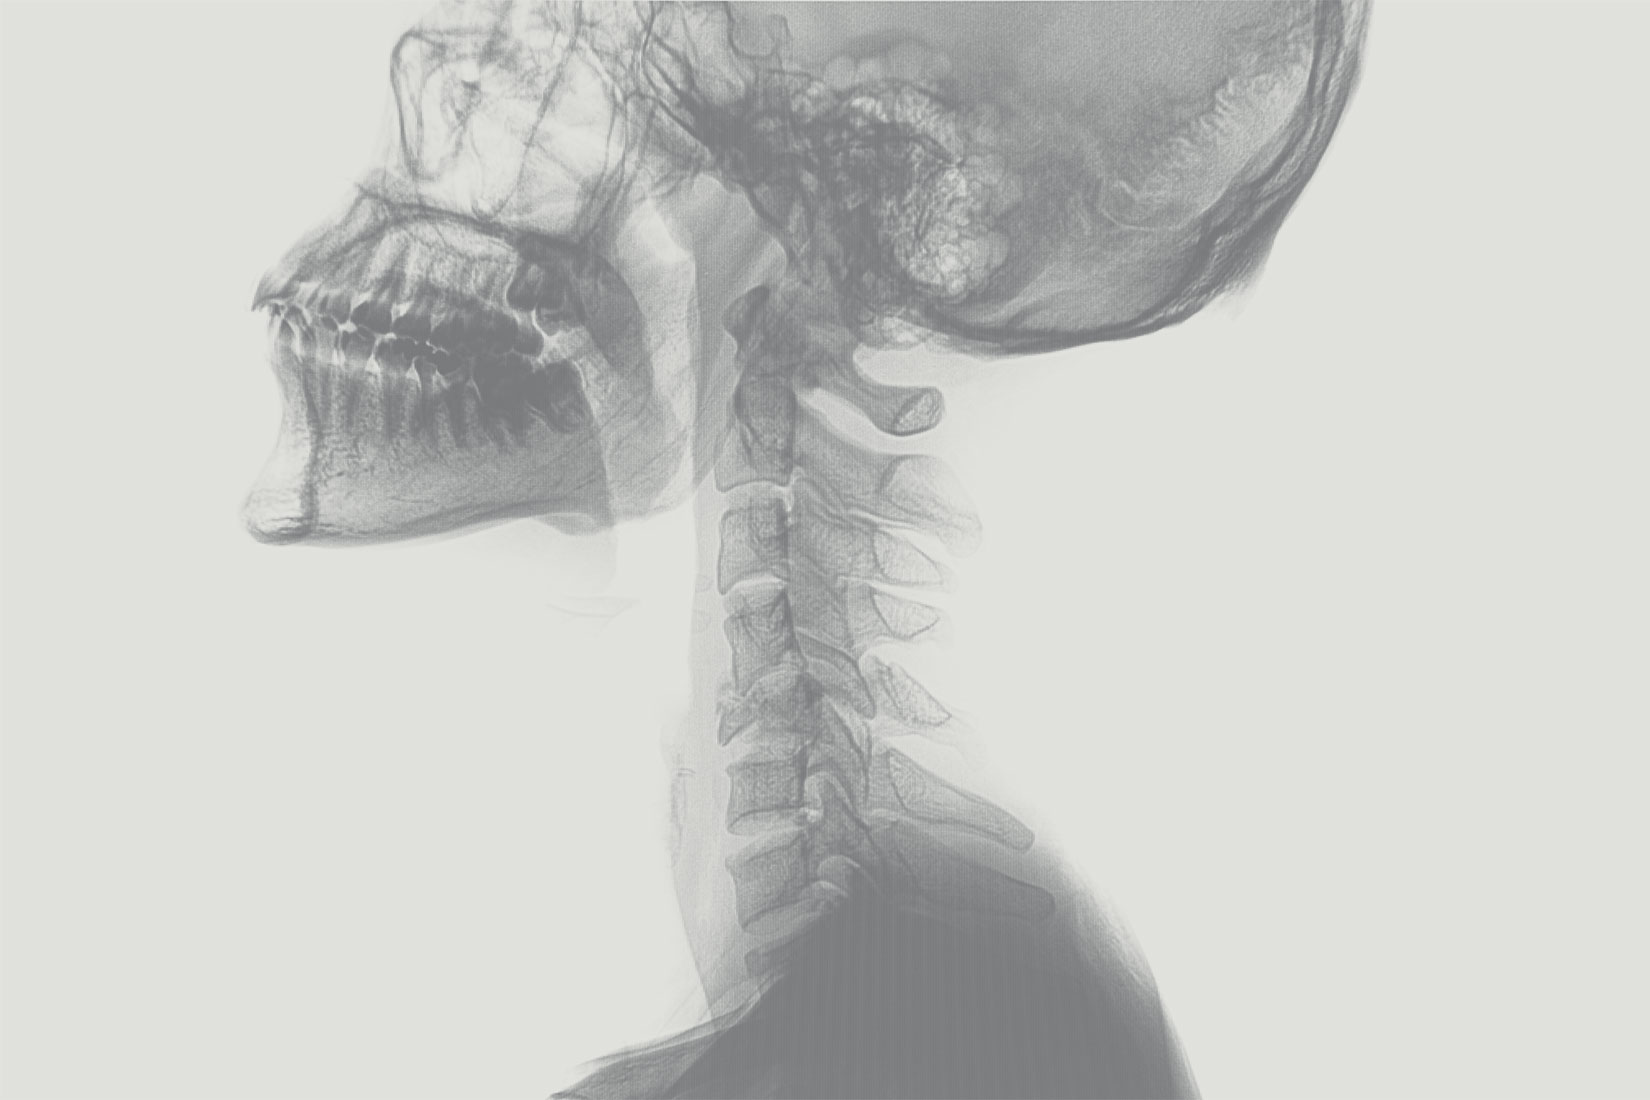

MEDIZIN

PHYSIK

EXPERTEN

Wir bieten Ihnen eine Kooperation im Sinne der neuen StrlSchV §132 an - Optimierung, Qualitätssicherung und Beratung in der Röntgendiagnostik.